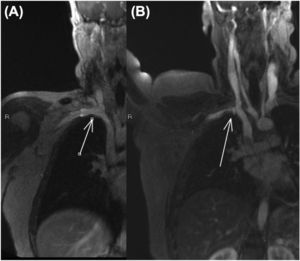

Dynamic magnetic resonance imaging (MRI) in abduction showed compression of the brachial plexus and subclavian vein at the costoclavicular space, which resolved in the anatomical position (Fig. 2).

Dynamic MRI showed complete occlusion of the left subclavian vein at the costoclavicular space with forced abduction of the limb.